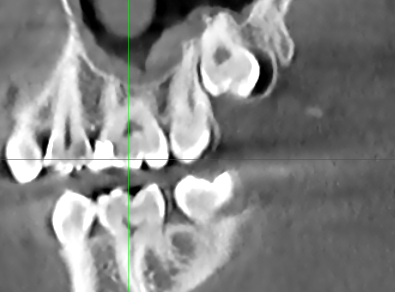

На 6 жевательном зубе справа на верхней челюсти в 2020 году поставлена пломба. Фото прилагаю. На КТ от 2024 года я сам нашел полость под пломбой, это вторичный кариес? Врач который смотрел КТ об этом не упоминал. Еще вопрос зуб же не депульпированный?

Все эти годы зуб не беспокоил. КТ скрины прилагаю.